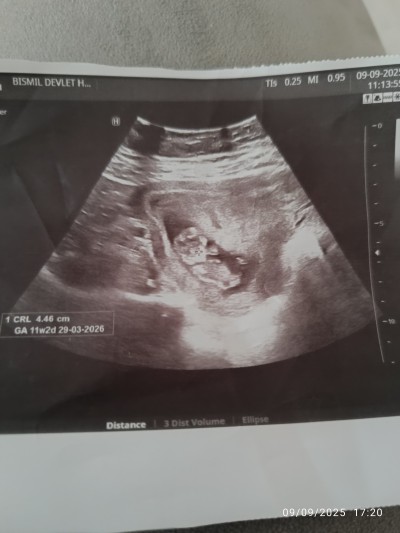

Kızlar bebisimin cinsiyet tahmininde bulunur musunuz beni bir heyecan sardı 🙂

Gebelik haftası 11 + 2